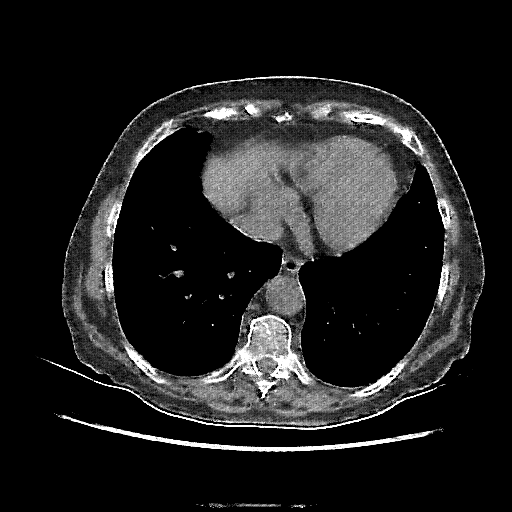

Original NATIVE CT scan (input)

Full window (WL 1023.5, WW 4095 β†’ Low βˆ’1024, High +3071)

Reconstructed NATIVE CT scan (cycle consistency)

Original VENOUS CT scan

Generated VENOUS CT scan (A→B translation)